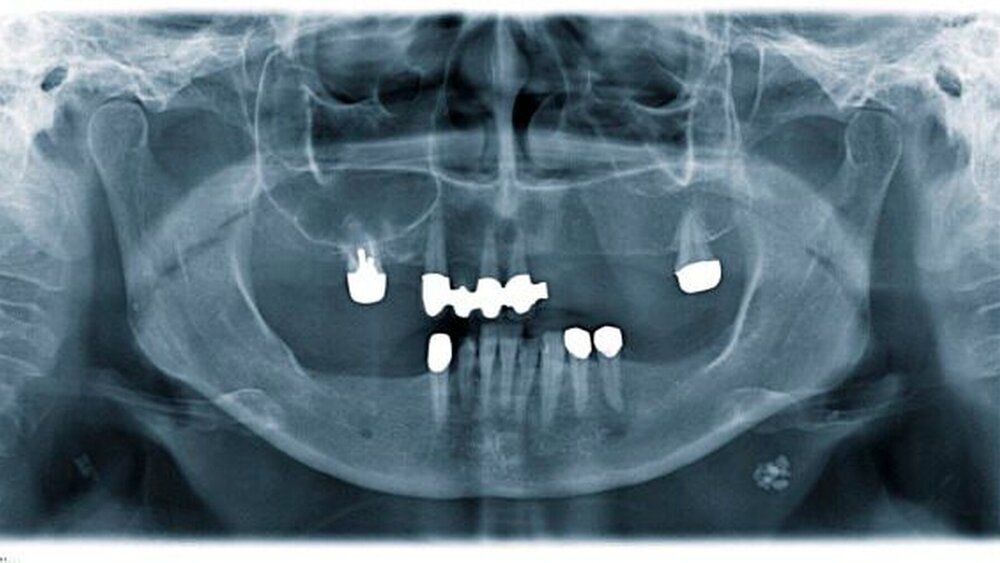

Eine 49-jährige Patientin stellte sich in der Schmerzambulanz zur weiteren Therapie vor. Aufgrund einer submukösen Abszedierung in regio 045 und eines Wurzelrestes in regio 027 wurde ein Orthopantomogramm zur weiteren Diagnostik angefertigt (Abbildung 1).

Dabei imponierten neben der periradikulären Aufhellung in regio 045 mehrere unregelmäßig angeordnete, wolkige, begrenzte Strukturen im Bereich des rechten und linken aufsteigenden Unterkieferastes. Außerdem waren unterhalb des rechten Ramus mandibulae in Höhe des Os hyoideum und im Bereich des linken Ligamentum stylomastoideum röntgenopake Strukturen sichtbar. Anamnestisch berichtete die Patientin von einer abgelaufenen Tuberkulose der Speicheldrüsen im Kindesalter, deren Spätfolgen im Sinne von Kalzifizierungen anhand der radiologischen Befunde palpiert werden konnten.